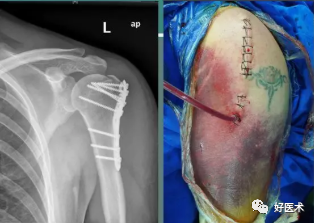

2.锁定板固定:

-

适用肱骨近端粉碎性骨折

不容易出现螺钉松动、退钉等情况,碎骨片固定后不容易发生二次移位

更适用于老年骨质疏松的患者

可以进行早期安全的功能锻炼

3.钢板螺钉内固定

对于骨质疏松的老年人三部分骨折,选用AO的LCP系统锁定钢板。